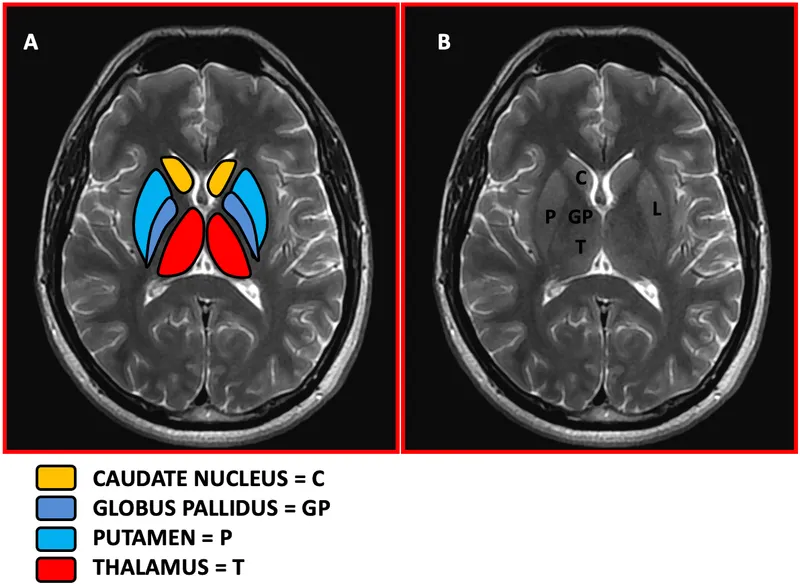

Basal Ganglia & Thalamus - The Core Nuclei

- Lentiform Nucleus: Comprises the putamen (lateral) and globus pallidus (medial).

- Striatum: A functional unit combining the putamen and the head of the caudate nucleus.

- Key Anatomical Borders:

- Internal Capsule: A critical white matter tract separating the thalamus (medially) from the lentiform nucleus (laterally).

- Caudate Head: Found anterolateral to the thalamus, characteristically bulging into the frontal horn of the lateral ventricle.